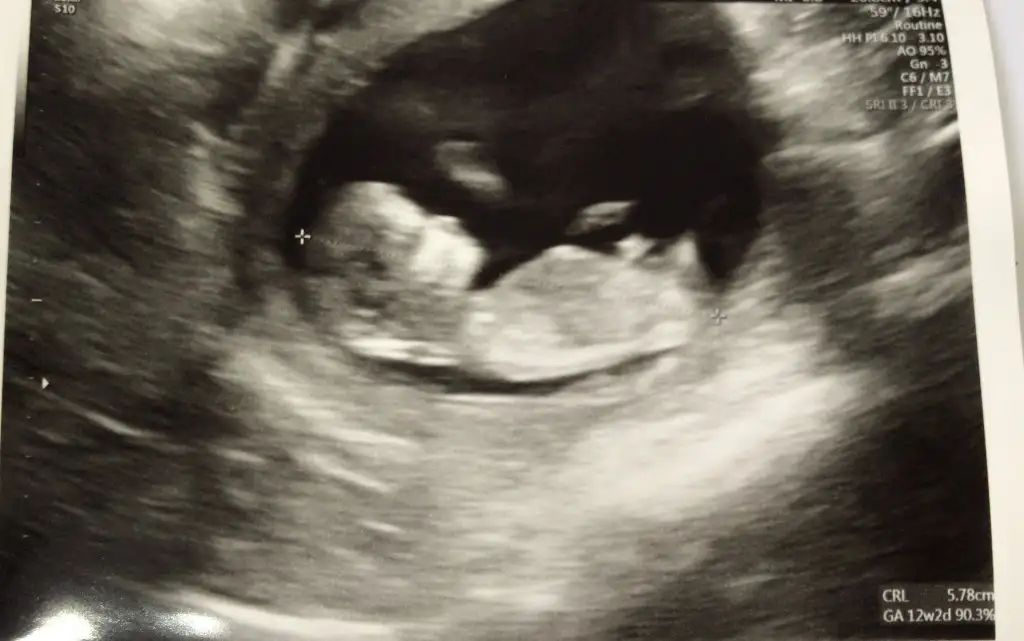

Bana da yorum yapabilir misiniz?

1.Resim 6+3

2.Resim 11+5

3.Resim 13+4

Arkadaslar burda çok yanlış yorumlar yapılmış sayfa baştan yanlış... Burada önemli olan bebeğin konumu değil plesanta inın konumu ramzi teorisine göre cinsiyeti belirleyebilmek için ultrason da bebeğin konumu değil plesantanın konumuna bakarak cinsiyet tahmini yapılmalı plesanta parlak olan beyaz kısma bakılarak anlaşılabilir